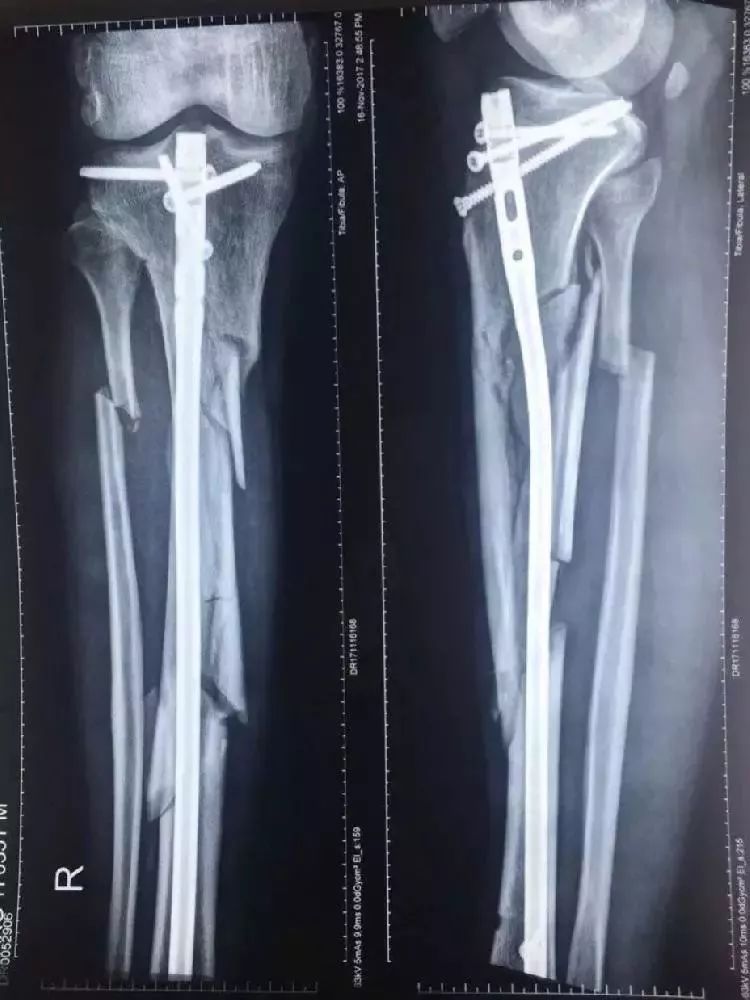

四个歹徒不容分说,在光天化日之下,用铁镐对着老人家就是一顿猛打,卧屮,铁镐啊大哥!必然是双腿粉碎性骨折(视频太残忍,慎入)。